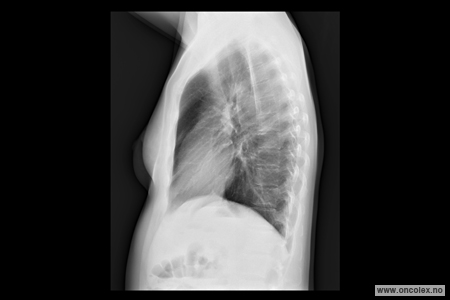

Røntgen toraks er en røntgenundersøkelse som tas for å se på lunger, hjerte og lymfeknuter i brystskilleveggen mellom lungene.

Under bildeopptaket står pasienten i en bestemt stilling foran røntgenapparatet.

Det tas bilder i front og fra siden.

Strålene som passerer gjennom kroppen treffer en sensor på den andre siden.

Røntgenbildet viser skjelett og lunger tydelig.